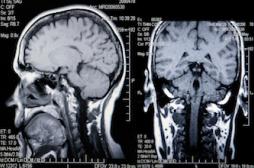

LES MALADIES

J'AI MAL